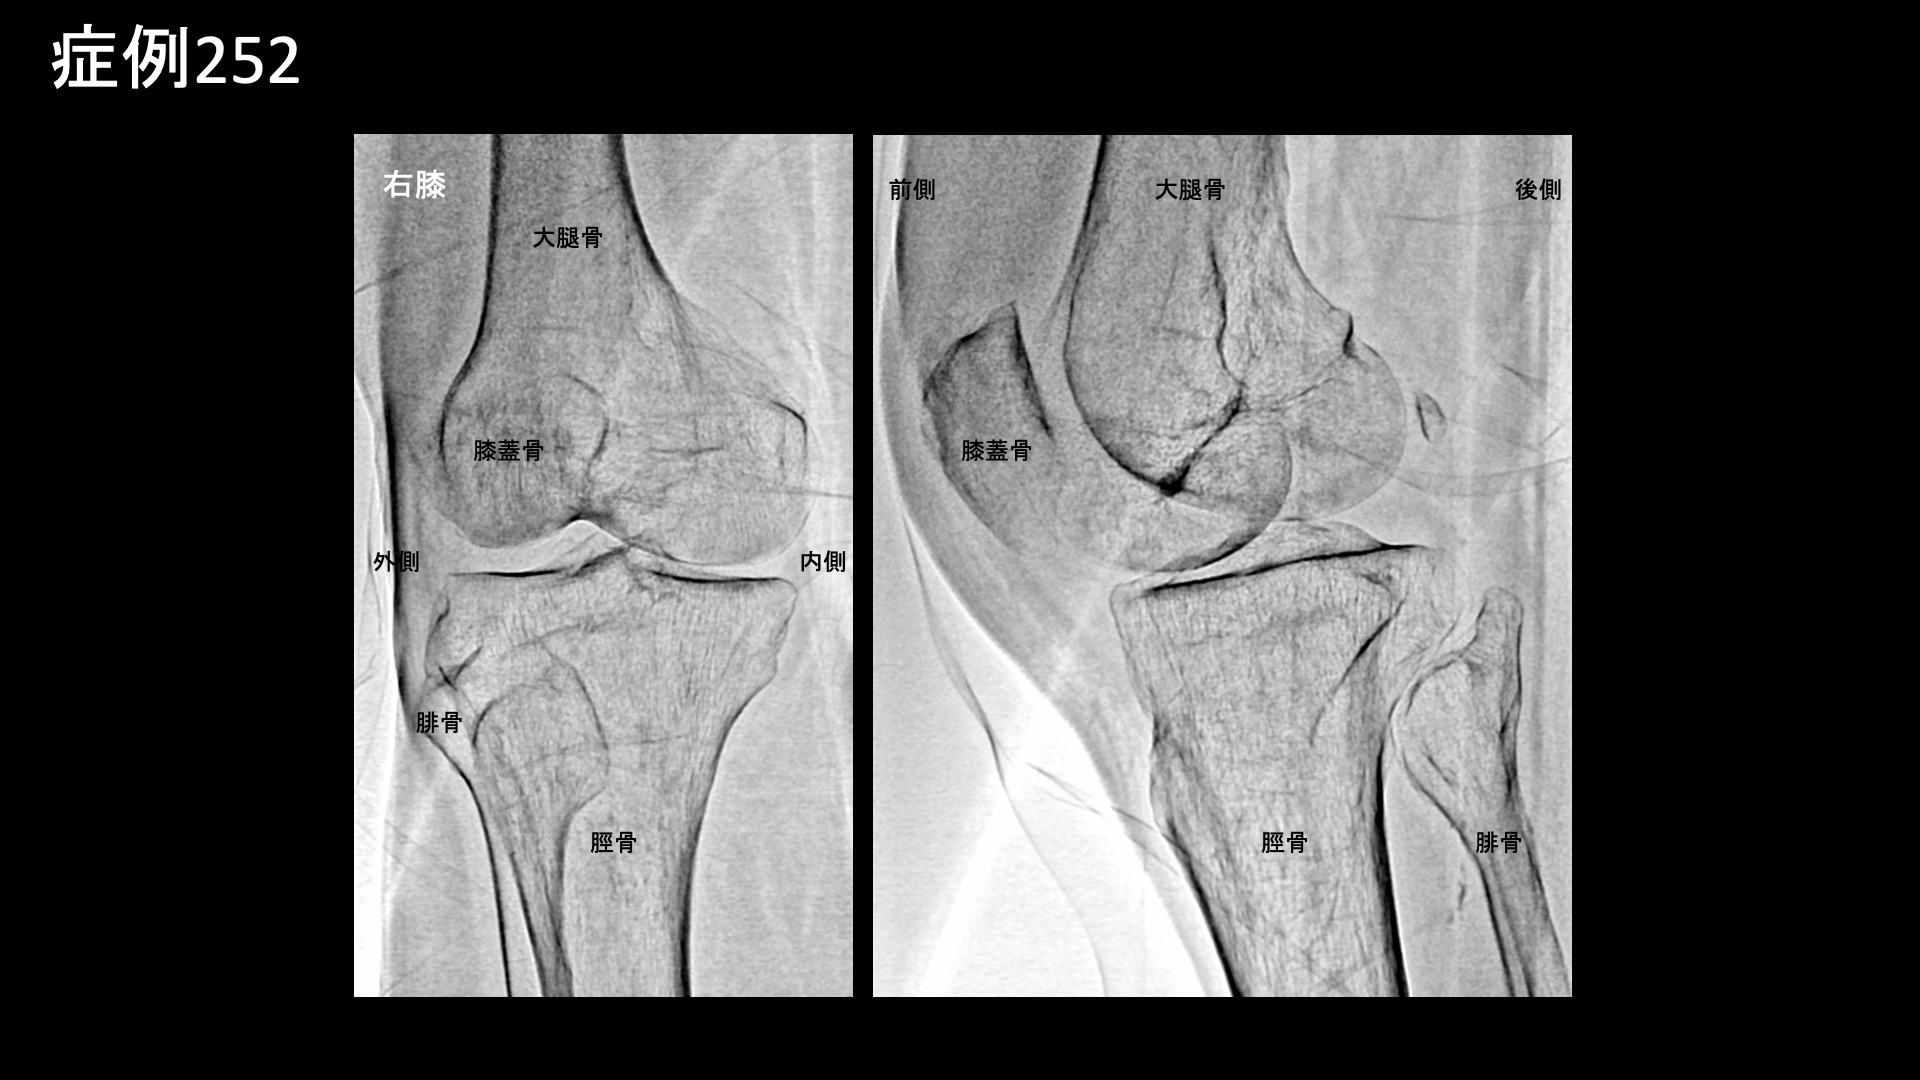

膝:変形性膝関節症など 【70代:男性】急激に悪化した膝の痛みで歩けなくなり夜も寝られず水も溜まる・・ネフローゼ症候群を合併した変形性膝関節症の実例(変形性膝関節症、ネフローゼ症候群) 2025.12.01 鴨井院長による動画解説 受診までの経過 それまで痛めたことはなかったのですが、3ヶ月前から急に右膝が痛み始めました。整形外科を受診し、水を抜いてもらいヒアルロン酸注射を受けていましたが改善しませんでした。松葉杖を使うほどの痛みにもなり、安静時にも痛むようになりました。ついには夜間に痛みで目が覚めるほどになりました。鎮痛薬も効かない一方で、外科手術の適応ではないと言われ思い悩んでいたところ、当院の治療を知り受診されました。 既往疾患;ネフローゼ症候群 診察時の所見 杖歩行にて入室されました。レントゲンでは中等度以上(KL分類3相当)の関節変形を認めました。エコー検査では、膝蓋上嚢に中等度以上の水腫を認め、その周囲や滑膜組織には炎症によるモヤモヤ血管を反映した異常血流信号が豊富に認められました。変形性膝関節症の診断ですが、病状は重症でした。基礎疾患としてのネフローゼ症候群が少なからず影響を与え、炎症が助長されていることが示唆されました。非常に強い炎症が関与していることから良い治療適応と判断し、モヤモヤ血管(病的新生血管)に対する運動器カテーテル治療(微細動脈塞栓術)を受けていただきました。 治療の所見 血管造影を行うと、外側上膝動脈、下行膝動脈などでモヤモヤ血管が濃染像として描出されました。治療後は画像上速やかに消失しました。その他複数箇所の治療を行い終了しました。 尚、強い炎症を反映して、治療時の再現痛は強めでした。 *再現痛とは、薬液投与時に普段の痛みが一定程度再現される現象です。責任血管の同定のための参考とします。 治療後の経過 治療翌日から改善しました。治療後3週間では、ほとんどの痛みが無くなりました。肩関節の可動域も完全に回復し、バンザイもできるようになりました。半年間苦しんでいた痛みのあまりの回復ぶりに、『最初からここに来ればよかった』と話されるほどでした。エコーで確認すると、まだ石灰沈着については大きな変化はありませんでしたが、今後吸収されていくことも期待できます。非常に経過良好であったことから、終診となりました。石灰沈着性腱板炎は強い炎症を伴っていることが多く、その苦痛も五十肩以上になることが少なくありません。カテーテル治療は強い炎症にこそ、強い効果を発揮します。実際に、本症例では非常に早期から快復しました。罹病期間が長くなければ、石灰も吸収されて無くなります。 非常に良い適応疾患の一つですので、お悩みの方はぜひご検討いただくと良いと思います。 治療前画像:損傷を受ける、あるいは繰り返しのストレスにより発生した異常な新生血管 治療後画像:カテーテルを用いて塞栓物質を血管内に投与し新生血管を塞いだ状態 治療費用:治療する部位によって費用が異なりますのでこちらをご参照ください。 主なリスク・副作用等:針を刺した場所が出血により腫れや痛みを生じたり、感染したりすることがあります(穿刺部合併症)。造影剤によるアレルギー(皮膚のかゆみ・赤み・息苦しくなるなどの症状)が出ることがあります。 変形性膝関節症の詳細 【50代:男性】最初からここに来ればよかった・・ステロイド注射無効で半年間苦しんだ石灰沈着性腱板炎による肩の痛み(石灰沈着性腱板炎、肩関節周囲炎) 前の記事 【40代:男性】新型コロナウイルスワクチン接種後、3年に亘り続いたしつこい肩の痛み。石灰沈着性腱板炎後遺症に対するモヤモヤ血管治療(石灰沈着性腱板炎後遺症、SIRVA、新型コロナウイルスワクチン接種) 次の記事